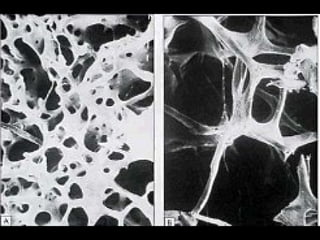

壓力性骨折 Stress Fracture 疲勞骨折 Fatigue fracture   骨質不良性骨折 Insufficiency fracture http://www.emedicine.com/radio/topic783.htm

the failure of the skeleton to withstand submaximal forces over time.  the failure of the skeleton to withstand submaximal forces over time.  http://www.mypacs.net/repos/mpv3_repo/viz/full/17093/854689.jpg